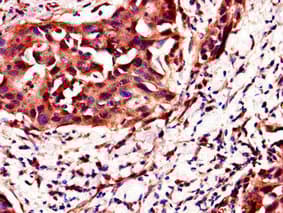

Anti-C4orf26 antibody(ab223071)

Rabbit Polyclonal C4orf26 antibody. Suitable for IHC-P and reacts with Human samples. Cited in 1 publication. Immunogen corresponding to Recombinant Fragment Protein within Human Odontogenesis associated phosphoprotein aa 1 to C-terminus.

Applications IHC-P

Species Reactivity Human